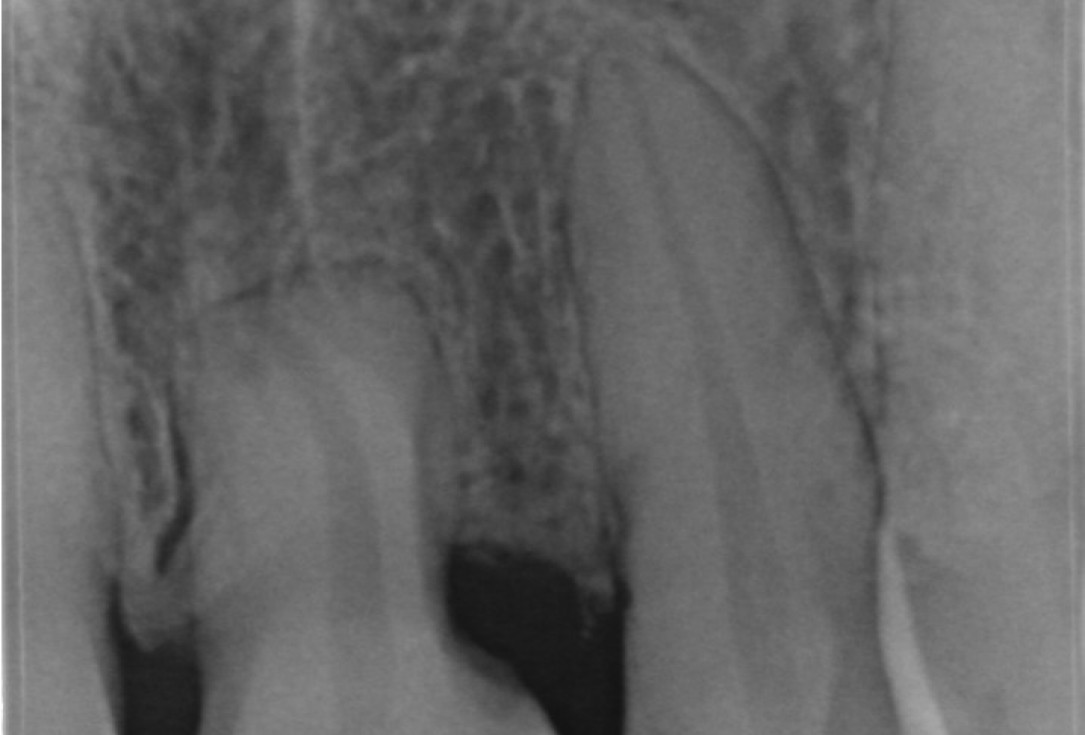

Immediate implant placement with cerabone® and mucoderm® - Dr. F. Rossi - X-ray of tooth 11Immediate implant placement with cerabone® and mucoderm® - Dr. F. Rossi

recession on tooth 11